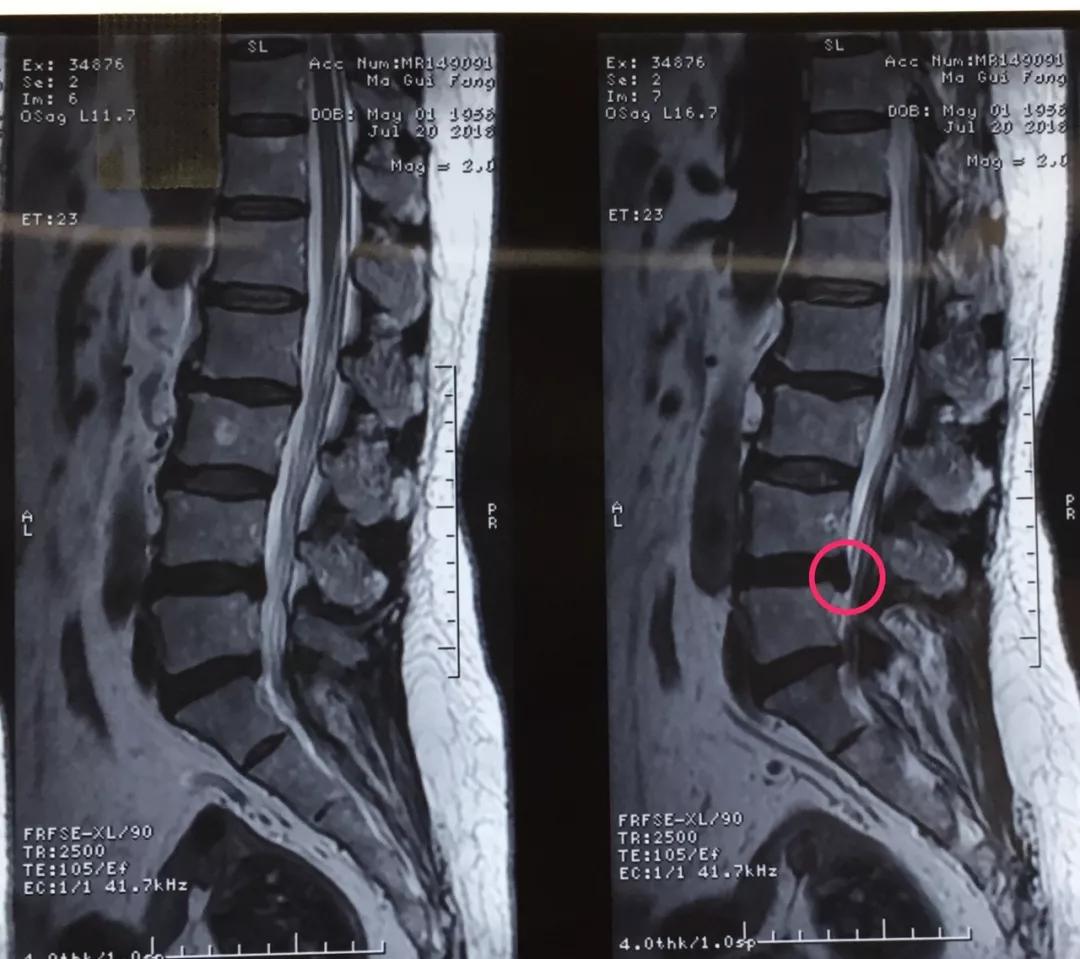

近日,市中心医院骨一科完成了院内首例椎间孔镜日间手术,手术耗时短,痛苦小,术后患者恢复良好。

60岁的人生状态应该是退休在家,带着孙子孙女享受天伦之乐,而同样是60岁的马老太,被腰椎间盘突出症困扰了多年,稍微劳累就腰背酸痛,近几个月来又开始出现左下肢的过电样抽痛,抽的腿都抬不起来,家人带着马老太到医院做了检查说是腰椎间盘突出症,问了几家医院都说要来开刀手术,卧床两月,这下把马老太吓住了,一边是病痛折磨,一边是对手术的恐惧,正绝望之际,邻居建议马老太到六合彩生肖 郭华副院长的专家门诊看一下,马老太并没有抱太大希望,那么多医院都说要手术,估计治疗方案是一样的,手术是免不了了。到中心医院后,郭华副院长仔细地询问了马老太的病史,并进行了细致的查体,然后看了看片子,对马老太说:“你这个情况确实是腰椎间盘突出症,但是不需要全麻开大刀,局麻下1cm小口把椎间盘取出来就可以了,术后就可以直接下地走路了,而且你现在检查齐全了,当天住院、当天手术、当天出院,我们叫做——椎间孔镜日间手术”,马老太半信半疑的回家考虑了几天,最终马老太还是相信中心医院的实力,24日马老太入住骨一科后,郭华副院长、严少荣主任、姬钢主任医师中午共同为马老太局麻下实施了经皮椎间孔镜下髓核摘除术,手术共计一小时,手术完马老太抬腿就不痛了,郭华副院长告诉马老太,你这个情况完全可以出院走路回家了,可把马老太高兴坏了。

郭华副院长介绍:随着人口老龄化,腰椎间盘突出症的发病数量越来越多,而医学的进步也同样日新月异,传统的开大刀手术越来越少,六合彩生肖 开展的经皮椎间孔镜下髓核摘除术(PELD)是近几年来成熟起来地一种微创手术方式,局麻下不到一小时就可以取出压迫神经根的椎间盘,术后即刻解除疼痛下地走路,甚至可以做到日间手术(当日住院、当日手术、当日出院),医保报销后花费少,效果立竿见影,得到了广大患者的认可和好评。希望医学德进步给广大病患带来福音,希望六合彩生肖 的新技术能为更多的病人解除病痛。